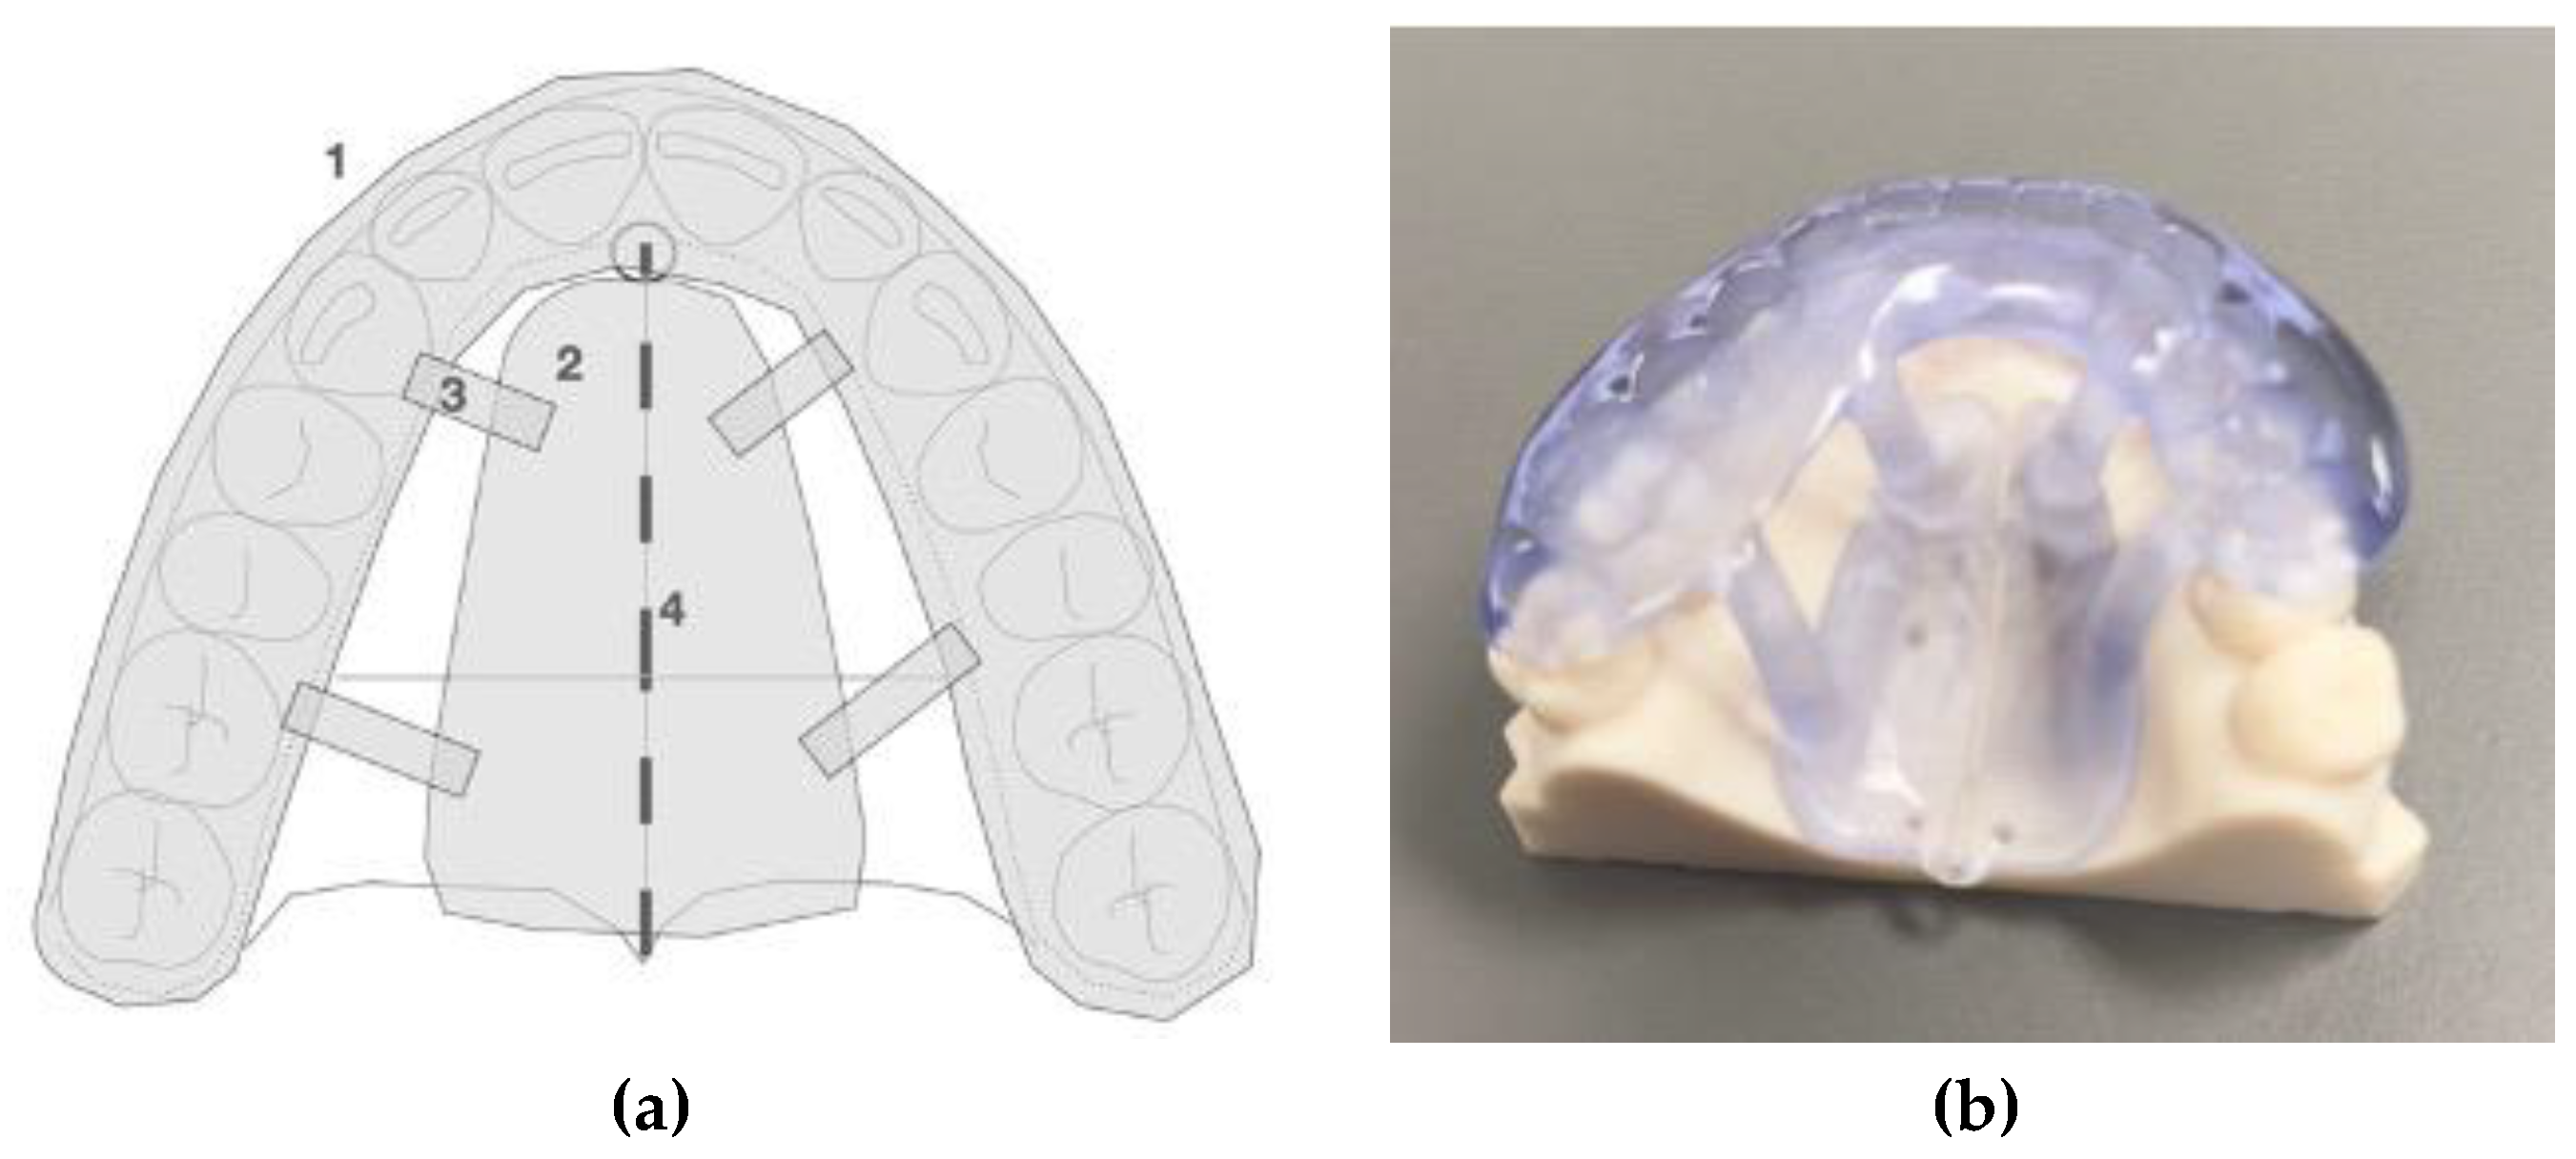

2.2. Description of the Novel Piezocorticotomy Guide for Midpalatal Skeletal Expansion

2.3. Technique of the 3D Printed Guide-Assisted Midpalatal Piezocortictomy